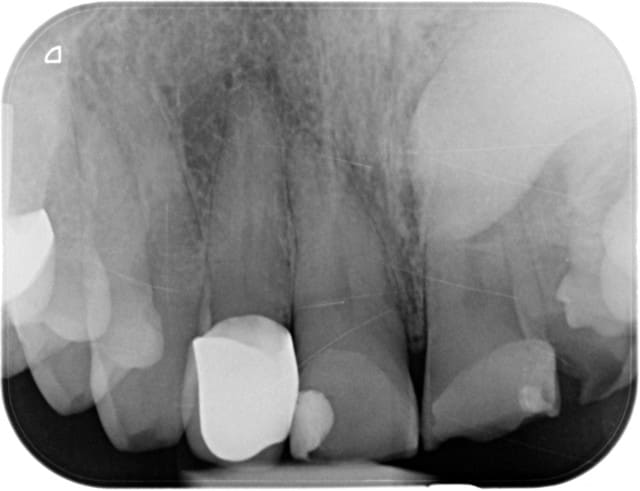

Je vois bien qu'il y a des images sous 16 et racine M de 36, mais 12 ?

12 TEST AU FROID

12 test au froid? sur une couronne?

test à la percussion + palpation, bien que ne LIPOE est pour moi objectivable à la radio...

on dirait qu'il y a une peche sur 35 e , je reviens à a canine incluse: test au froid sur 22 au cas ou...

Pour 12, y.a pas à tortiller du c.. Les gars, il y a une lésion apical. Tu passes à travers, et tu endo. Emax ds 4 mois.

12 : RAS à la percu, aucun symptôme. Mais sur la radio l'image est quand même assez nette. Je vais percer je pense et j'espère que je n'aurais pas trop de mal à trouver le canal.